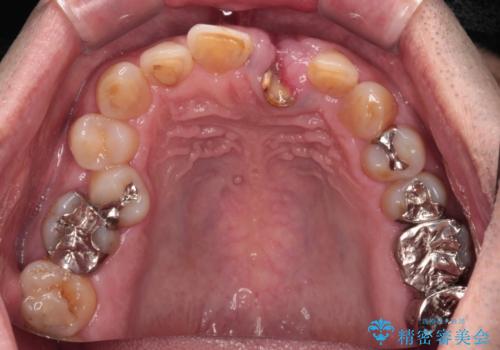

- 歯が朽ちてしまい、歯茎に大きな溝ができていることを気にして来院された患者様です。

インプラント治療を希望されておりましたが、軟組織の欠損が非常に大きいため、骨の回復を待ちながら歯肉の形態を整えていくこととしました。

歯肉形態を概ね回復するタイミングでインプラントを埋入し、補綴治療を行うこととしました。